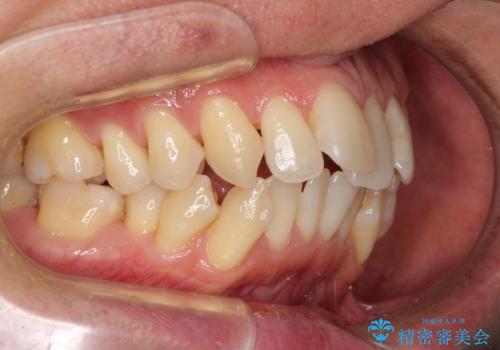

今回の治療では、奥歯が前方に傾斜した歯並びだったため、奥に起き上がることで歯列が後方に移動し、横側からも口元が引っ込んだ感じが分かるほど改善されました。